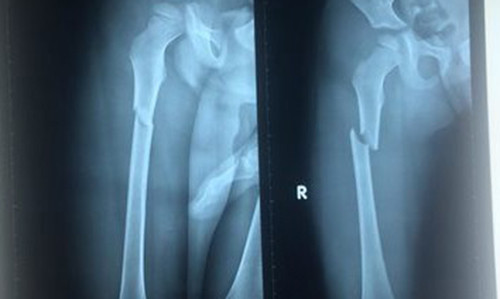

| Phim chụp X-quang chân Thiện bị gãy. Ảnh: Khánh Trung. |